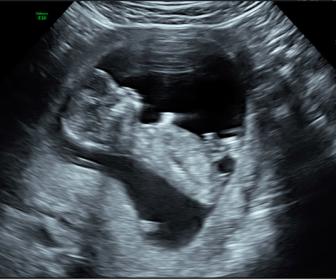

Hi all, would love any opinions on whether our first is a little boy or girl? (12w5d) Thanks so much! :) Attachment 37532Attachment 37533

I can't see the nub real well but it looks angled so boy guess from me.

Thanks for taking the time to post your thoughts ksmom & gabrielsmummy90. Initially I thought girl based on the first photo, but the second photo confused me... is that what you'd call a stacked nub? Thanks :) x